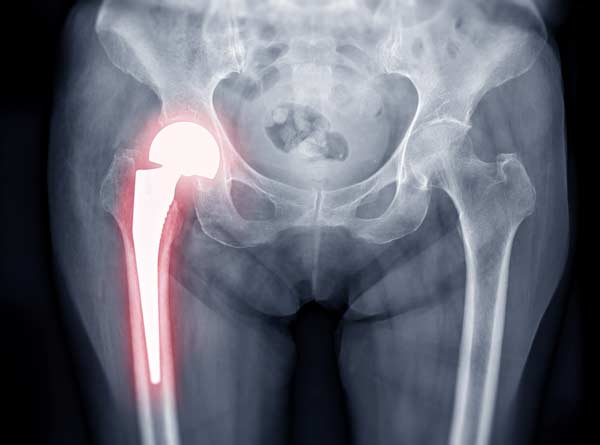

Exactech trató de ahorrar dinero en el empaque del producto. El aire oxida (degrada) los revestimientos de polietileno de los implantes de Exactech. Este revestimiento, que es exclusivo de estos implantes, es básicamente cartílago artificial. El fabricante lo llama amortiguador. Esta absorción de impacto ayuda a que estos dispositivos duren mucho más que los implantes metálicos. Entonces, el revestimiento es más que cosmético. Si falla un inserto, falla el reemplazo de la articulación.

Sin el acolchado protector, los implantes articulares esencialmente se desmoronan debido al desgaste excesivo. El polietileno no es tan tóxico como otros tipos de plástico, principalmente porque no contiene BPD. Sin embargo, todavía es tóxico en algunos casos. Los desechos del propio implante podrían causar problemas similares de envenenamiento de la sangre.

A medida que el dispositivo se deteriora y el tejido circundante se inflama e infecta, los dispositivos migran fuera de sus lugares designados. Al principio, la incomodidad del paciente no es tan mala.

Muy rápidamente, el dolor se vuelve debilitante y la mayoría de las personas pierden la movilidad que habían ganado y se hace necesaria una cirugía de revisión.

Un médico debe abrir el cuerpo del paciente y extraer el implante. Dado que este implante ahora está en pedazos en todo el cuerpo, esta cirugía es larga y difícil. Luego, si el paciente quiere otra articulación artificial, el médico debe reemplazarla minuciosamente sin dañar más el tejido circundante que ya está débil.